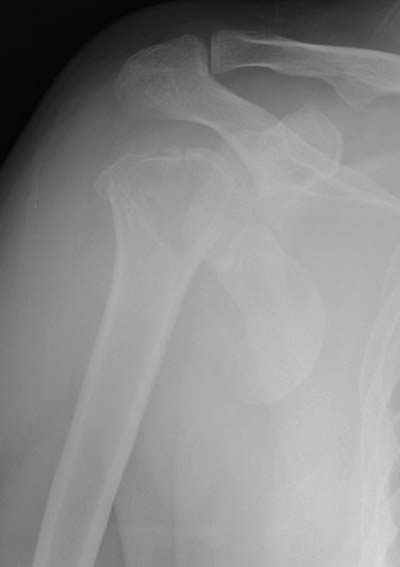

Женя, а как ты водишь спицы, в смысле, как делаешь входное отверстие, и как в него проводишь V-спицу? А то о дна из спиц, та, у которой не дошла до головки одна палочка буквы V, как-то выглядит на рентгенограмме, как будто или через очень большое отверстие введена, или каждая половинка через отдельные отверстия.

В чем ты видишь причину вторичного смещения?

Мне кажется, проблема в том, что не все концы спиц зашли в головку, и зашедшие - недостаточно далеко прошли.

Спицы провожу по передней и задней поверхностям плечевой кости через 4,5 мм отверстия на разных уровнях.

Идеей презентации случая была демонстрация важности постоп Рг - хотя казалось бы все было сделано под флюороскопическим контролем и интраоперационно подозрений на нестабильность не возникло, а такая вот

неожиданность...

V-спица проводится через 4,5 мм отверстие. Видимо, из-за разной длины вторая половина спицы *пролетела* мимо отверстия, что и привело к вторичному смещению костных фрагментов.